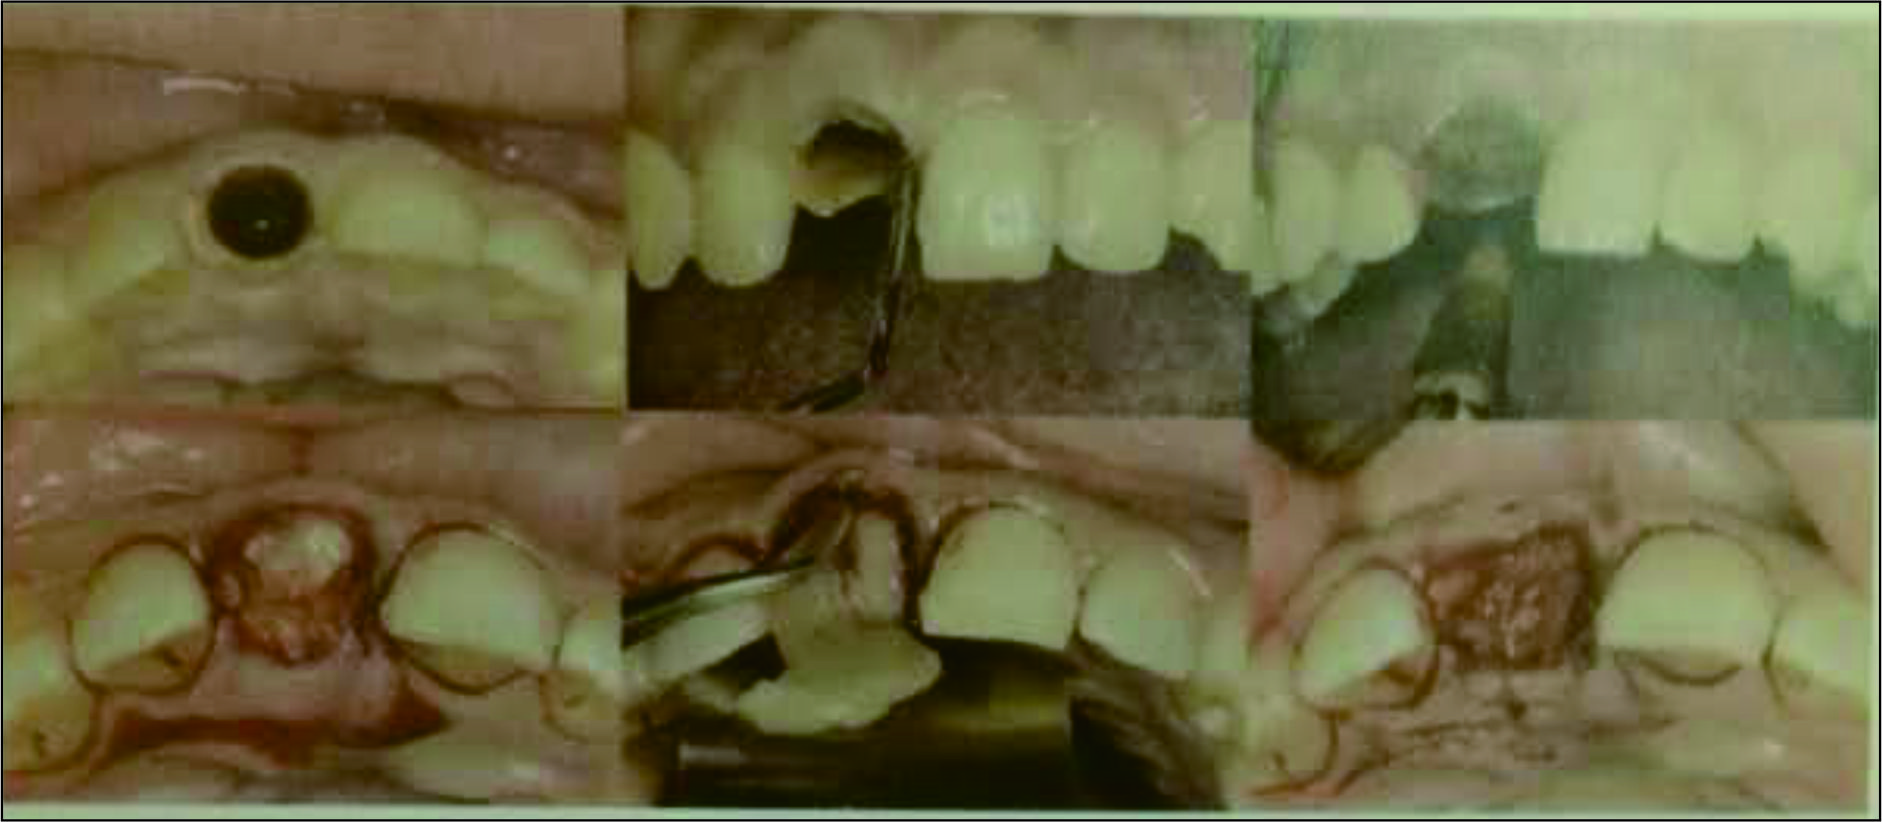

用Periotome分离牙周膜,颚侧近远中微创拔牙挺挺出残根,四周骨壁完整,仔细搔刮拔牙窝肉芽组织,直至新鲜骨面,大量0.9%NaCl冲洗,放入制备好的CGF纤维蛋白凝块,并覆盖CGF纤维蛋白膜,强生快薇乔可吸收缝线十字交叉缝合,10d拆线,见图3。

图3 微创拔牙及牙窝内CGF充填

拔牙8周后进行种植体植入术,保留牙龈乳头切口,翻瓣,可见已有部分唇侧骨板吸收,形成三壁骨缺损,丰满度下降,拔牙窝中间仍有部分空虚,在种植体植入的合适位置3.0环钻取骨,样本送组织切片观察,在取骨区骨挤压后植入士卓曼3.3x13mmNC(士卓曼,Switzerland)种植体一枚,扭力15N.cm,唇侧使用CGF混合BIo-Oss骨粉(Geistlich,Switzerland)过量植骨增加丰满度,上方覆盖Bio-Guide可吸收膜(Geistlich,Switzerland),减张缝合。手术图步骤详见图4-6,

术中过量植骨,术后可见唇侧丰满度膨隆。术后骨组织切片见图7,

拔牙窝最中间仍未有新骨,但四周已有较成熟新骨形成,新生骨小梁结构分布均匀,代谢活跃,成骨由拔牙窝周边向中央进行。